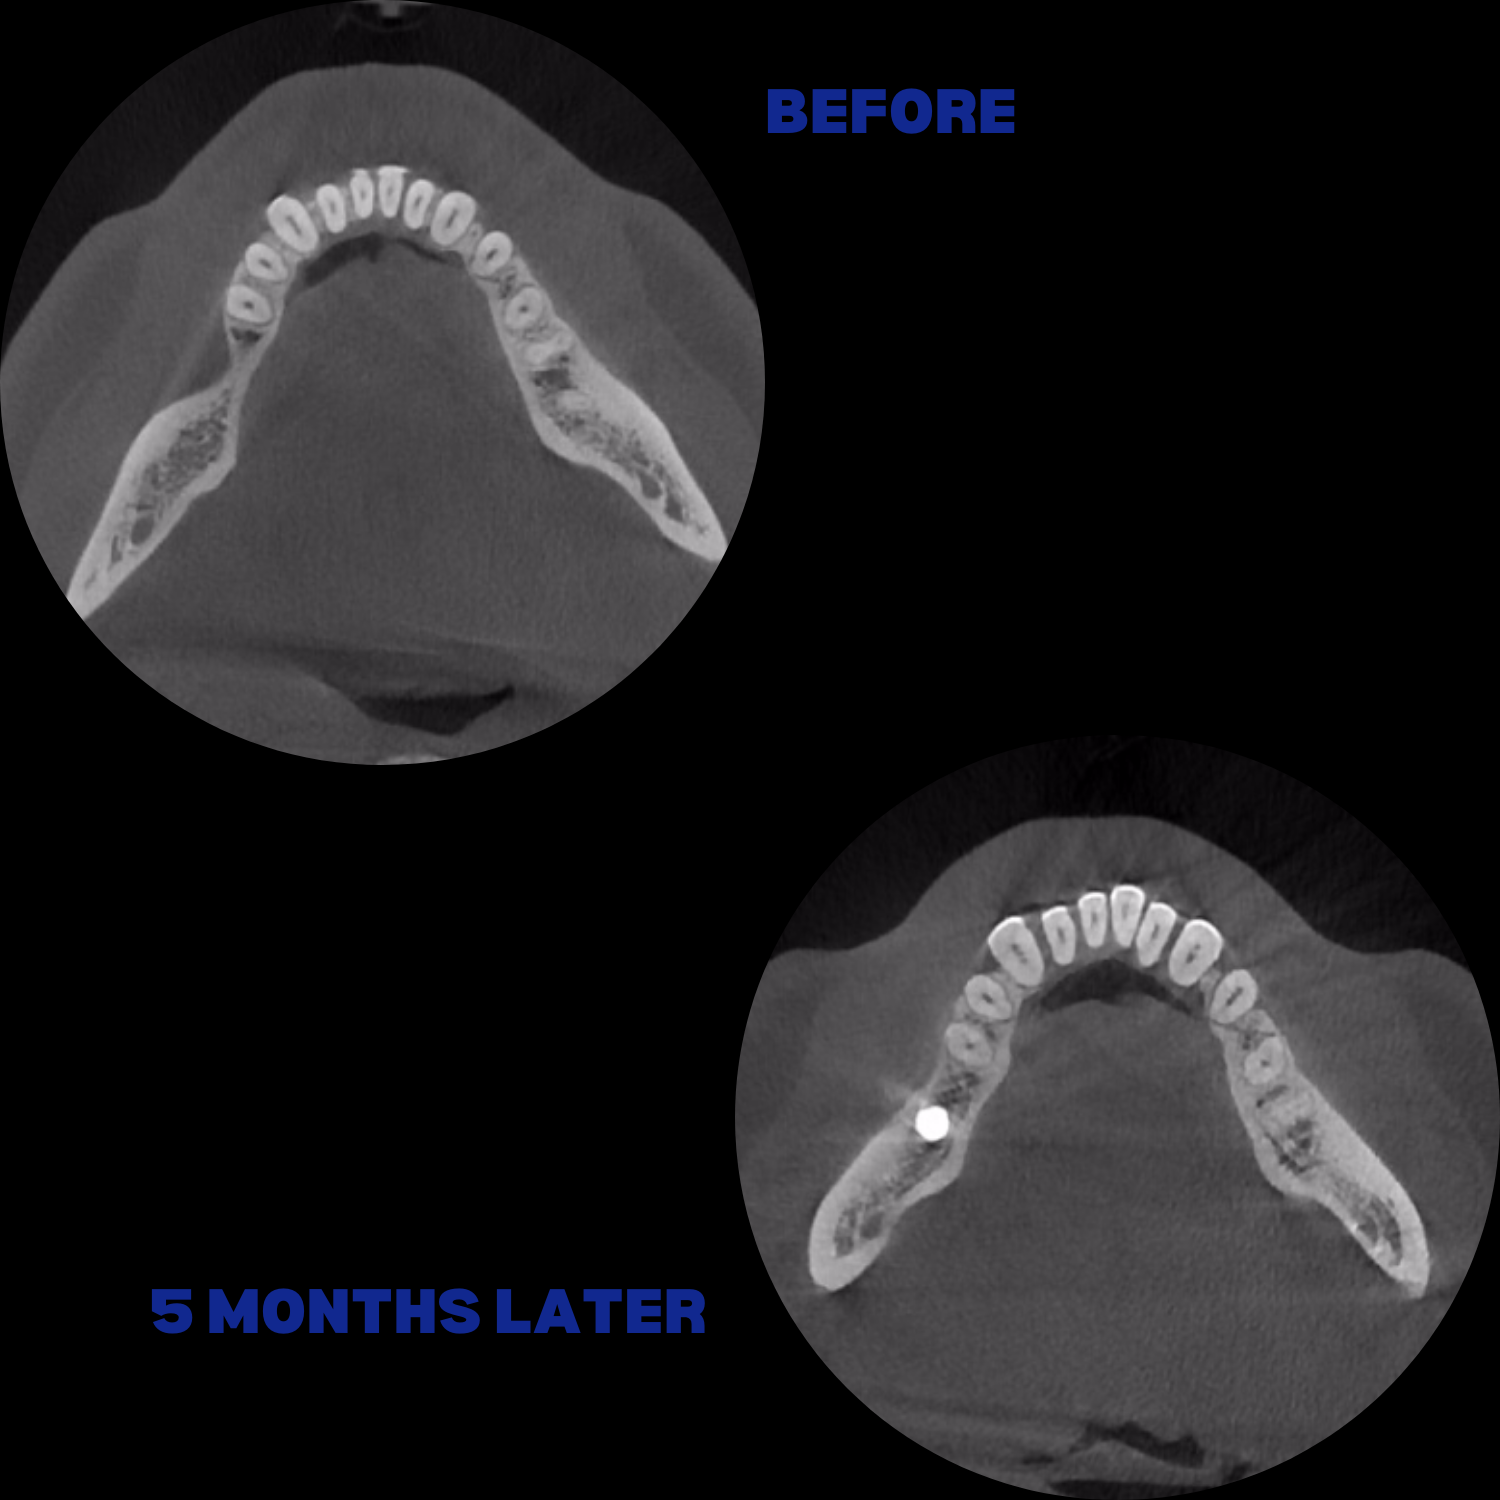

İmplant etrafındaki kemik açıklığını kemik grefti ile tedavi ettiğimiz vakamız.